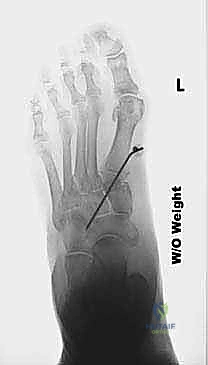

التصوير الطبي والتشخيص الإشعاعي المتقدم

لا يكتمل التشخيص الدقيق دون الاستعانة بأحدث تقنيات التصوير الطبي. يحرص الأستاذ الدكتور محمد هطيف على استخدام نهج شامل يتضمن:

- الأشعة السينية أثناء تحمل الوزن (Weight-bearing X-rays): وهي المعيار الذهبي. يتم أخذ صور من الأمام والخلف والجانبين أثناء وقوف المريض. تسمح هذه الصور بقياس الزوايا بدقة، مثل زاوية ميل الكاحل، وزاوية ميري (Meary's angle)، وتحديد موقع ذروة التشوه.